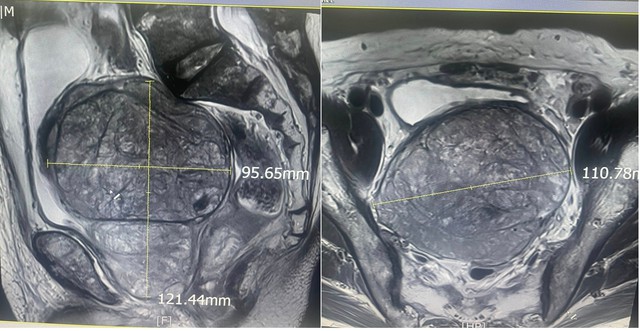

Phẫu thuật thành công tuyến tiền liệt "khủng" 600 gram cho bệnh nhân 83 tuổi. Đây là 1 trong những khối u tuyến tiền liệt lớn nhất từng được ghi nhận ở Việt Nam.

Trước phẫu thuật, bệnh nhân nhập viện trong tình trạng tiểu khó kéo dài, bí tiểu tái diễn nhiều lần, kèm theo rối loạn tiêu hoá do khối u tuyến tiền liệt khổng lồ chèn ép trực tràng.

Tuy nhiên, từ sau tuổi 40, tiền liệt tuyến thường có khuynh hướng phát triển bất thường, được gọi là phì đại lành tính tiền liệt tuyến hay tăng sinh lành tính tiền liệt tuyến. Tuyến tiền liệt bị phì đại sẽ làm hẹp và tắc lòng niệu đạo, dẫn đến rối loạn tiểu tiện như tiểu khó, bí tiểu, tiểu nhiều lần…